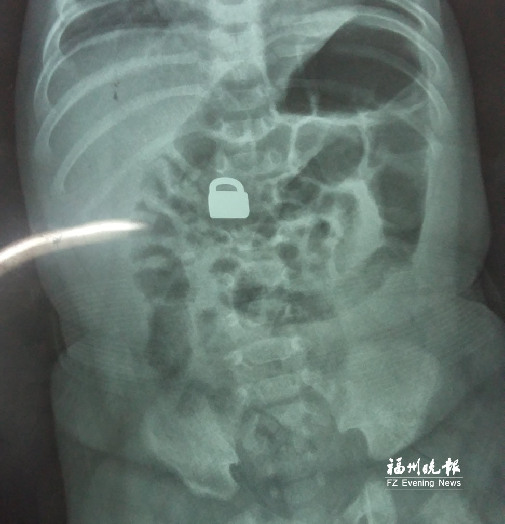

7.25龍巖當(dāng)?shù)蒯t(yī)院拍的X光片顯示,平安鎖在寶寶體內(nèi)。

這名60天大的“神奇寶寶”來(lái)自龍巖,哥哥也只有兩歲。7月25日,兄弟倆的媽媽突然發(fā)現(xiàn)寶寶胸前掛著的平安鎖不見了,便問(wèn)小哥哥是否看到弟弟的平安鎖。小哥哥回答,他把平安鎖塞到弟弟嘴里了。媽媽趕緊檢查寶寶嘴巴,沒有發(fā)現(xiàn)平安鎖。雖然寶寶沒有任何癥狀,但媽媽還是帶著他去當(dāng)?shù)蒯t(yī)院檢查。拍片結(jié)果顯示,平安鎖真的在寶寶體內(nèi)。

“X光片顯示,那是一把1.5厘米×0.9厘米的平安鎖,有指甲蓋大小,已經(jīng)到了寶寶的小腸處。”7月28日,陳惠萍見到寶寶時(shí),吃了一驚,“他真的好小,被抱在媽媽懷里,眼睛微微睜開,我估計(jì)他的世界還是混沌的,沒想到就已經(jīng)接受了這么大的挑戰(zhàn)?!?/p>